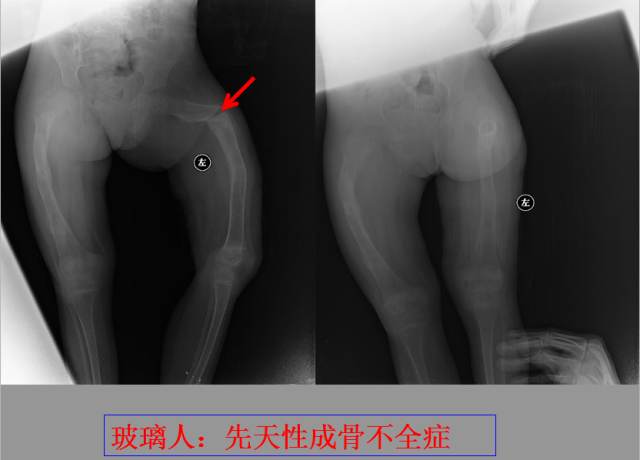

定义:骨折{Fracture}是指骨的完整性和连续性的折裂或粉碎。包括创伤性骨折、疲劳性骨折和病例理性骨折。 临床上以创伤性骨折*常见。